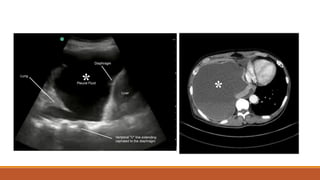

60/ Female

DM, HTN, CAD

SOB for 5 days

S3 Gallop present

ECHO- 25% EF

DIAGNOSIS?